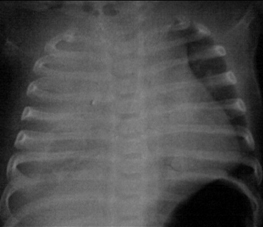

Taquipneia transitória do neonato (síndrome do desconforto respiratório tipo 2): estrias peri-hilares e fluido na fissura horizontal à direita

Do acervo de Ponthenkandath Sasidharan, MD; usado com permissão